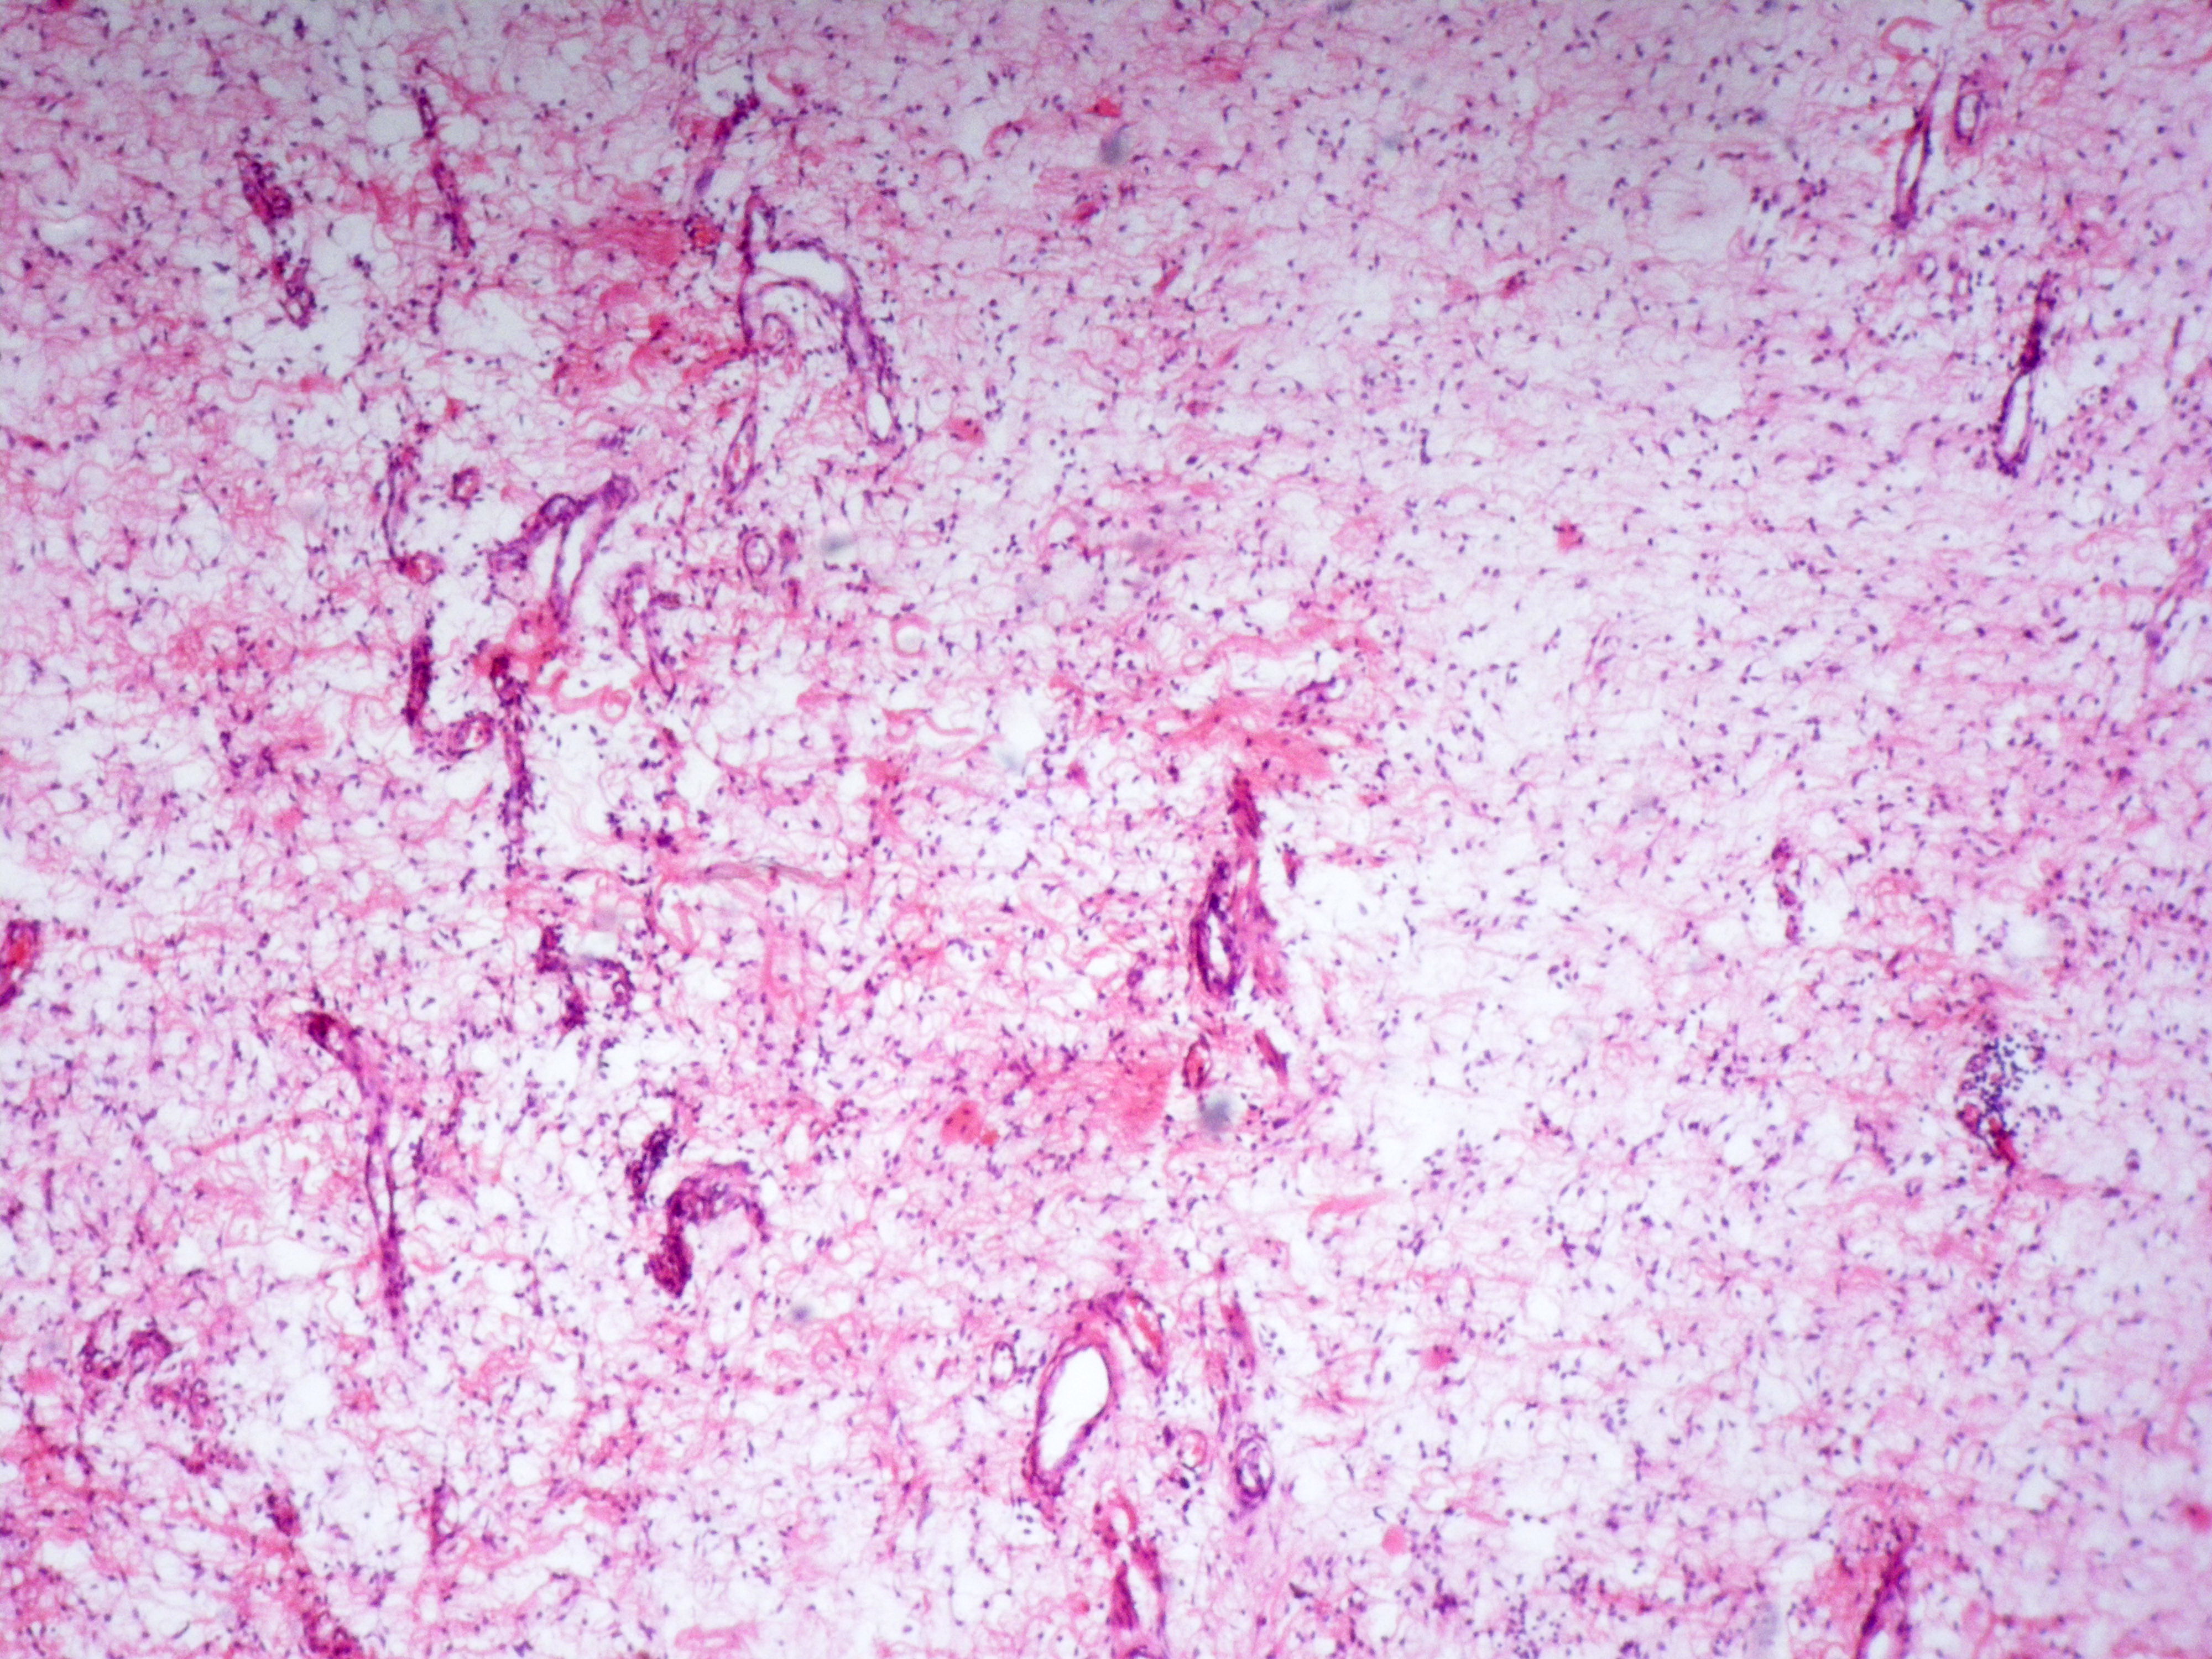

Fig 2: Histopathology showing hypocellular stroma and myxoid changes (x100).